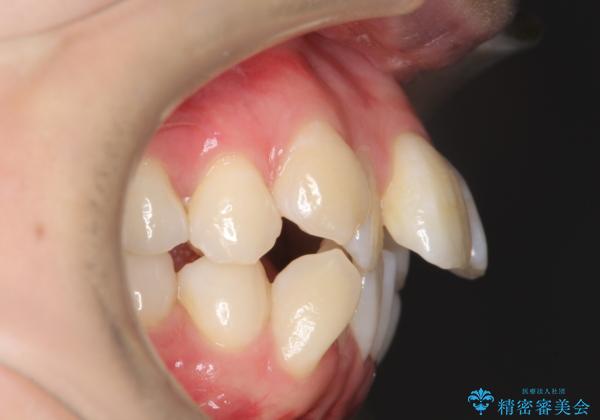

- 出っぱによる口元の閉じにくさを主訴に来院されました。上顎の出っ歯と上下顎叢生も認められたため、上下顎両側4番抜歯を行い、ワイヤー矯正で治療する治療計画を立てました。

上顎にはMI(マイクロインプラント)を埋入して固定源とすることで出っ歯の改善を図りました。

少しスペースクローズに時間がかかりましたが、MIを用いたワイヤー矯正で

主訴である出っ歯と叢生が改善されました。口も閉じやすくなり、スッキリとした口元になりました。